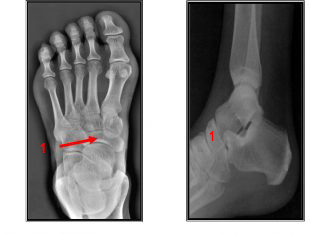

Mujer de 26 años de edad que acude a la consulta tras sufrir caída de su propia altura cuando caminaba a una fiesta; refiere inversión forzada del pie izquierdo. Durante la exploración física se observó aumento de volumen en la cara lateral del tobillo izquierdo y dolor localizado. Se diagnostica esguince del ligamento colateral externo de la articulación del tobillo. Se toma radiografía anteroposterior y lateral del tobillo. Se observó un trazo de fractura en la unión del maléolo lateral y la diáfisis de la fíbula.